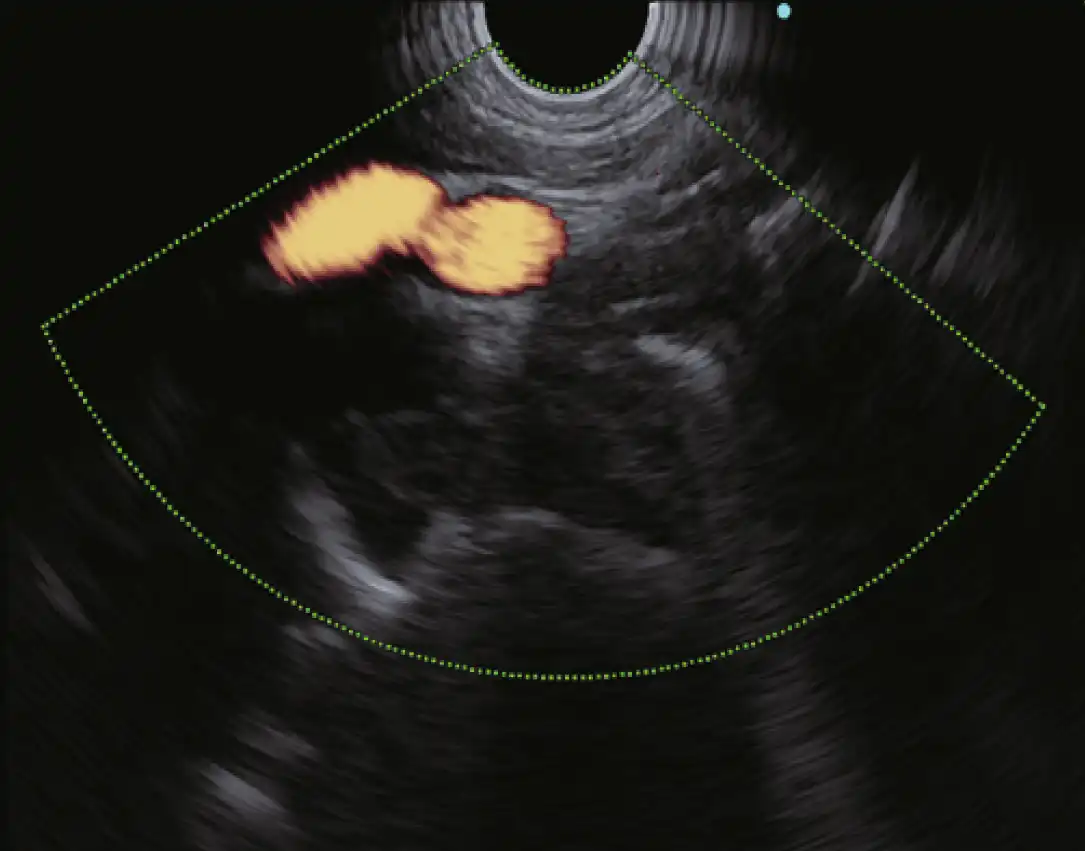

多普勒模式

EU-ME3 提供三种基本的多普勒模式,以更清楚地分辨血流--彩色血流、能量血流和脉冲波多普勒(PWD)。多普勒模式可用于支持更安全的手术,使病人和医生都受益。

除了三种基本的多普勒模式外,EU-ME3还具有H-Flow模式。H-Flow是一种更敏感的多普勒模式,可显示定向血流,且花纹较少。它对回声内窥镜尖端周围的小血管成像特别有用。